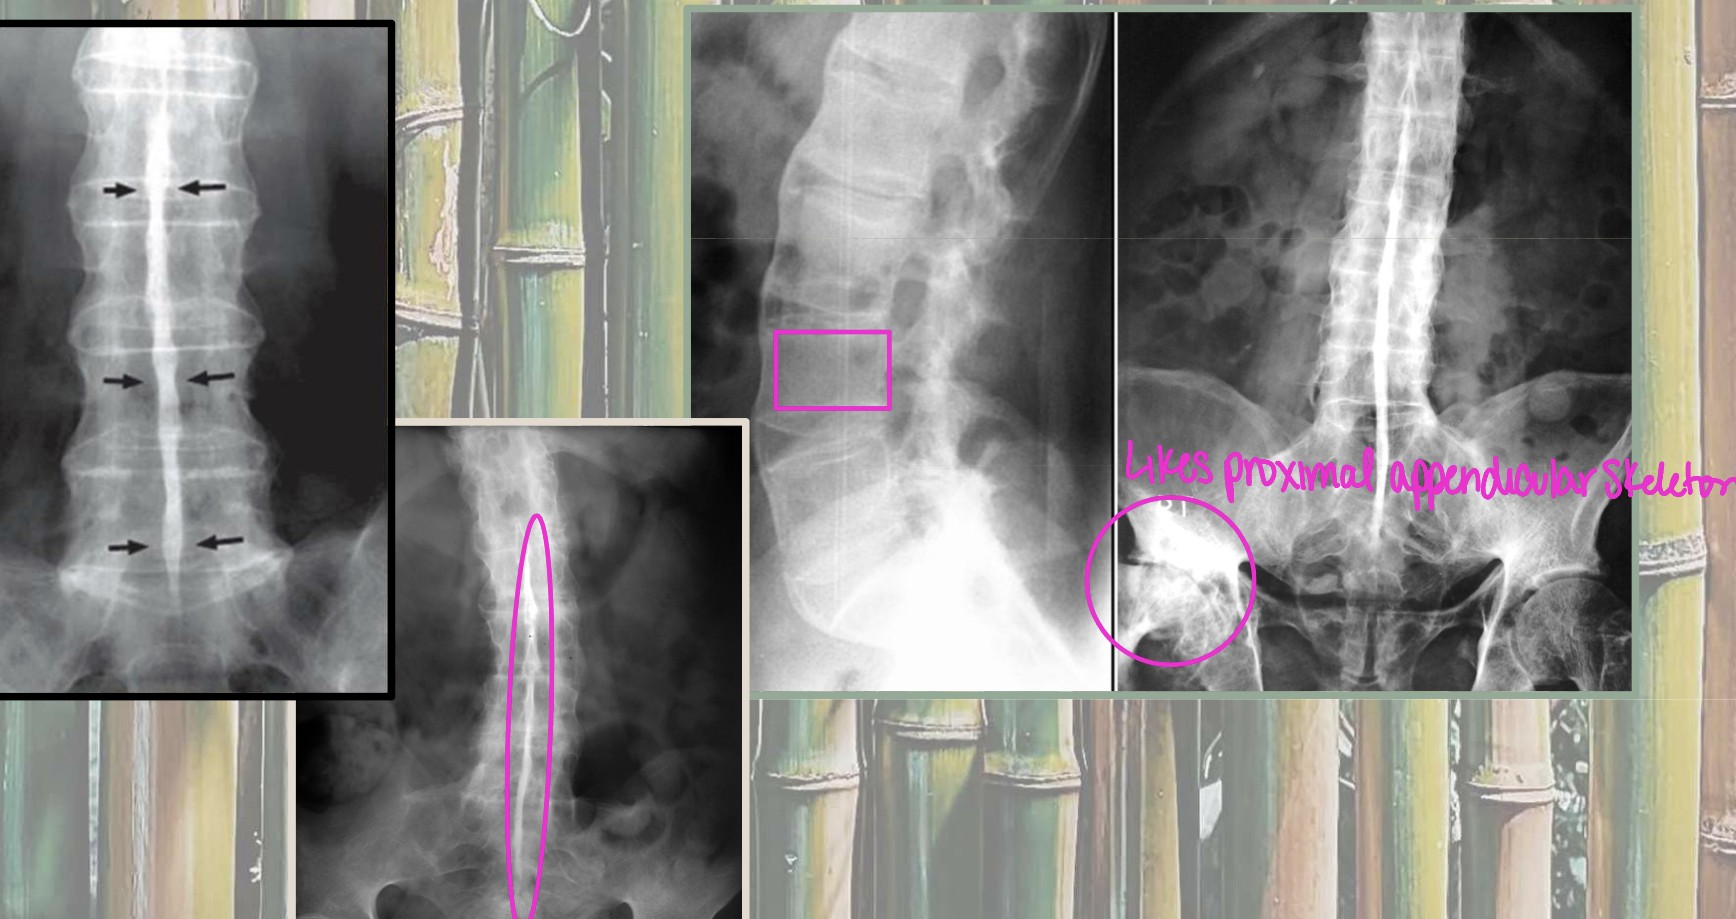

AS and Enteropathic arthritis syndesmophyte characteristics

symmetrical, thin, gracile/fragile marginal

PsA and Reactive arthritis syndesmophyte characteristics

asymmetrical, thick, bulky nonmarginal (above and below endplates)

What are the two dx of these images (left vs right)

Left = PsA

Right = AS